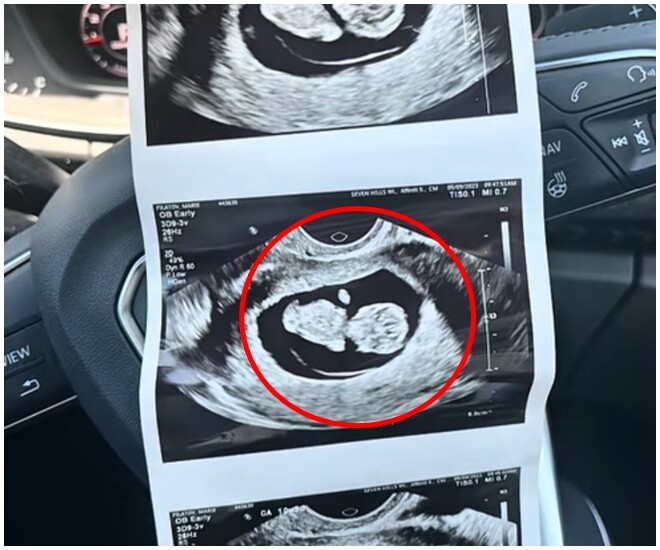

Khi biết rằng mình đang mang thai con đầu lòng, Marie Filatov tràn đầy háo hức cùng vị hôn phu Jack chờ đợi ngày được gặp con gái. Mọi chuyện diễn ra bình thường cho đến buổi siêu âm hình thái thai nhi ở tuần 20, thời điểm quan trọng trong thai kỳ.

“Tôi rất hạnh phúc khi sắp có đứa con đầu tiên. Nhưng buổi siêu âm hôm đó đã thay đổi tất cả. Khi bác sĩ kết thúc buổi siêu âm, ông quay lại nhẹ nhàng nói: ‘Mọi thứ đều ổn… chỉ có một điều, bé bị thiếu bàn tay trái’, Marie nhớ lại.

Kết quả siêu âm cho thấy em bé thiếu bàn tay trái.

Sau đó, bé Myla được chẩn đoán mắc khuyết tật giảm chi (limb reduction defect), một tình trạng hiếm gặp, ảnh hưởng đến khoảng 1 trong 2.100 trẻ sơ sinh ở Mỹ, theo Trung tâm Kiểm soát và Phòng ngừa Dịch bệnh (CDC). Dù dị tật này có thể gây hạn chế vận động hoặc thẩm mỹ, hầu hết trẻ bị khuyết tật giảm chi vẫn phát triển trí tuệ, thể chất và khả năng thích nghi bình thường. Nhiều em học cách sử dụng phần chi còn lại hoặc được hỗ trợ bằng chân tay giả, phục hồi chức năng, vật lý trị liệu để hòa nhập cuộc sống.

Các bác sĩ nghi ngờ nguyên nhân là do một sự cố mạch máu hoặc cục máu đông hình thành rất sớm trong thai kỳ, khi cánh tay bé đang phát triển. “Chúng tôi đã rất lo lắng, không biết cuộc sống của con sẽ ra sao. Nhưng tất cả nỗi sợ tan biến khi con chào đời”, Marie nhớ lại.